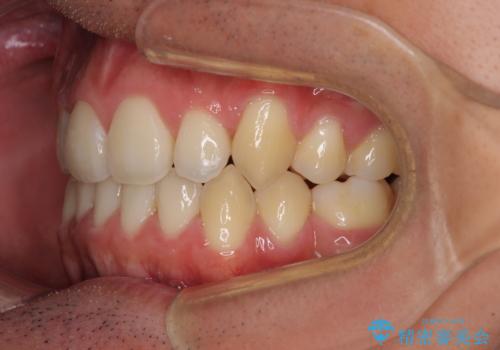

奥歯の咬み合わせの左右差が大きかったため、変則的な抜歯矯正を行いました。

治療期間はやや長期化しましたが、満足のいく歯並びとなりました。